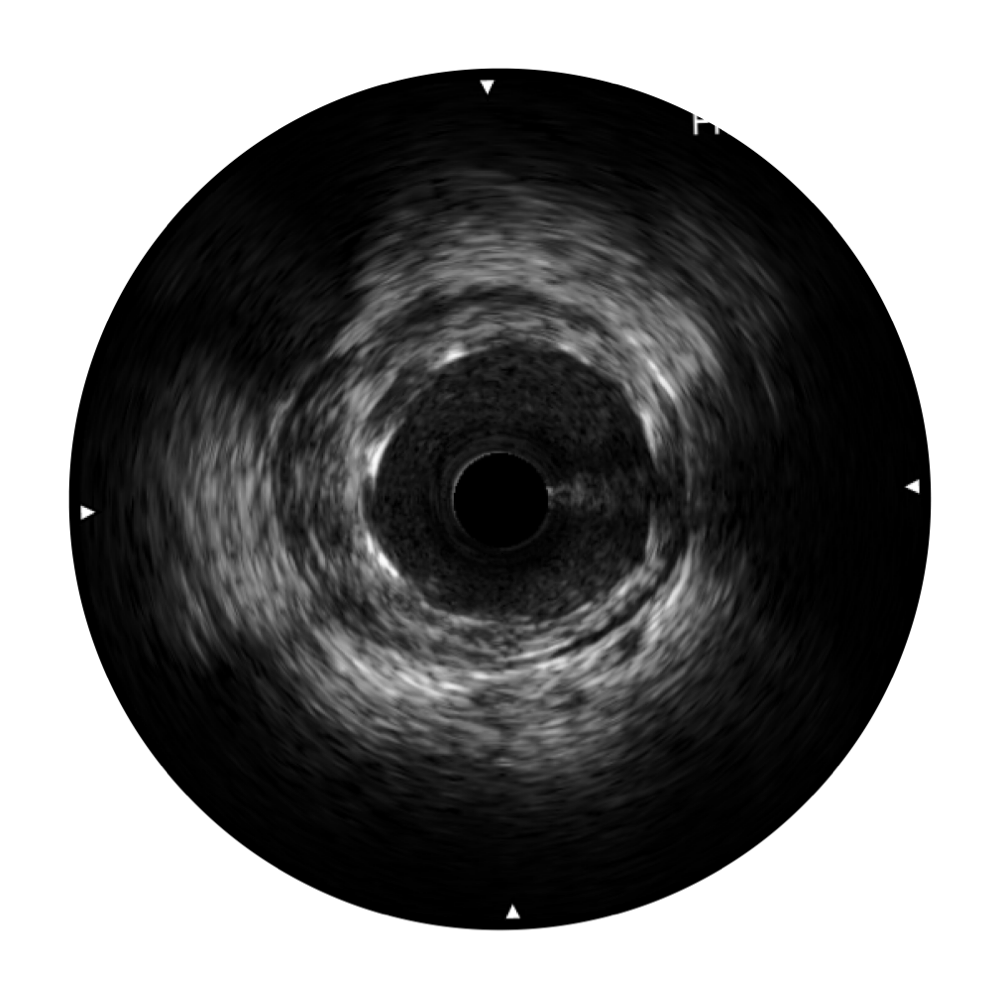

银河集团官网宽频IVUS图像

传统IVUS图像

对比传统IVUS导管成像,银河集团官网宽频IVUS图像的近场支架梁显影更细腻,远场中膜外血管仍清晰可辨,兼顾远中近,兼顾分辨力与穿透深度